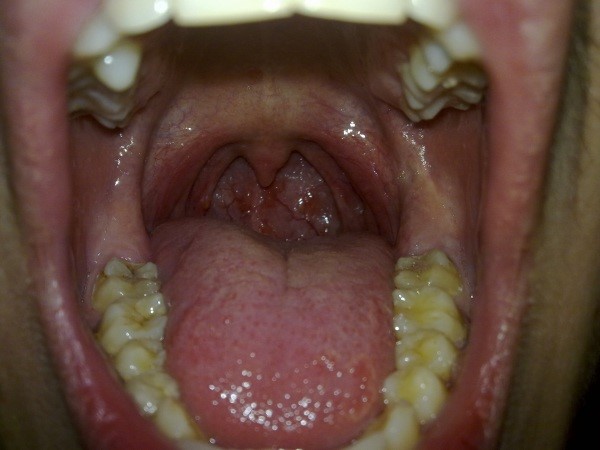

Абсцесс

Красные волдыри на задней стенке горла: что это? Возможно абсцесс! Это серьезное заболевание. связанное с гнойным воспалением горла. Возникает как следствие перенесенной ангины или травмы слизистой.

Появляются большие красные волдыри на стенке горла, которые со временем только увеличиваются. Они наполнены гноем. поэтому в домашних условиях их удалять ни в коем случае нельзя.

На горле красные волдыри: фото с гноением, каким бывает абсцесс: